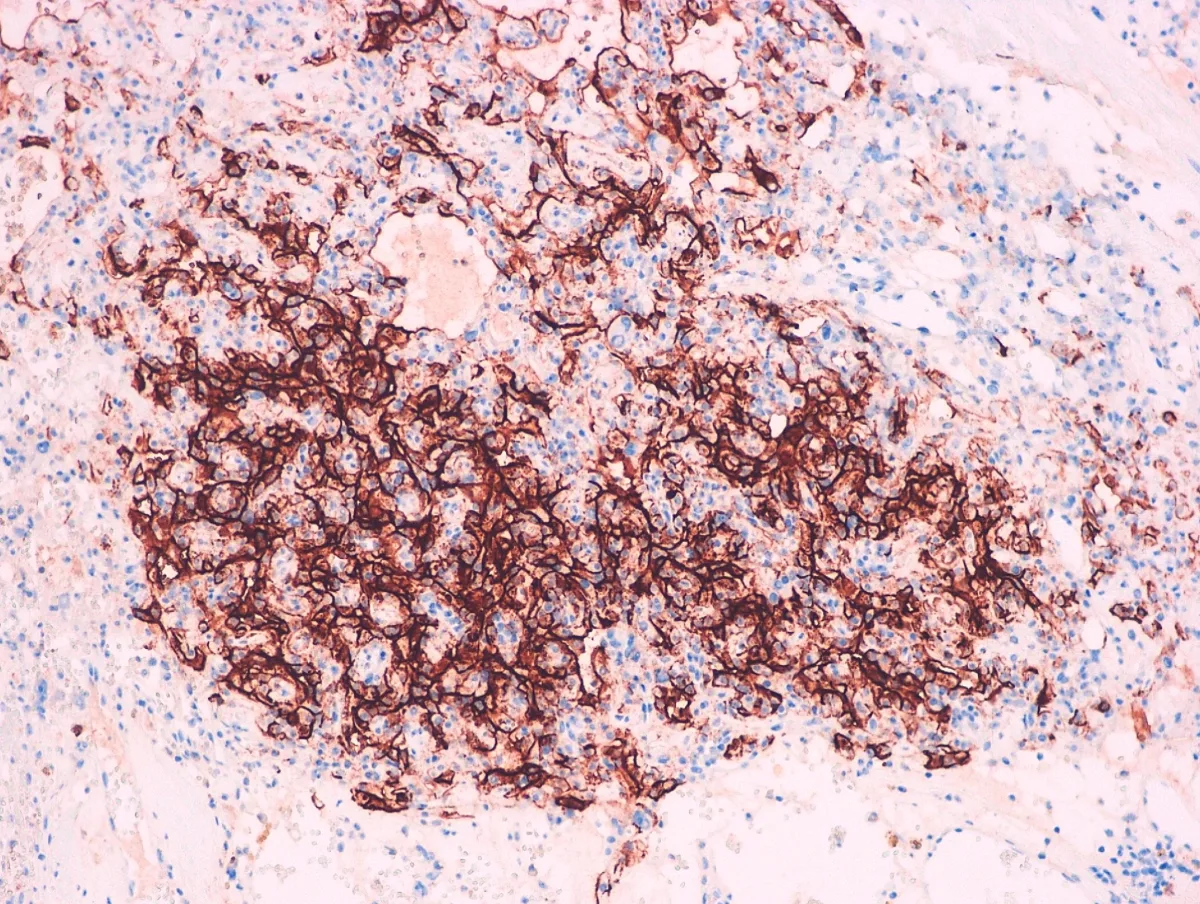

Diagnóstico: MESOTELIOMA EPITELIOIDE DIFUSO PERITONEAL

- Estos tumorales expresan Calretinina, Antimesotelio (HMBE1), Mesotelina, EMA, Trombomodulina, WT1, CK5/6, CK7, D2-40, Vimentina, Podoplanina y, en casos aislados, PAX-8 (PMID: 24183360).